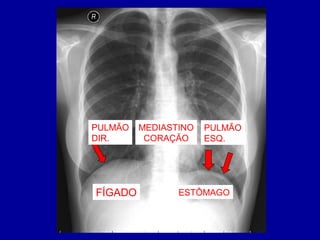

DIAFRAGMA

• SEPARAÇÃO ENTRE

TÓRAX E ABDÔMEN

• DUAS HEMI-CÚPULAS

• DIAFRAGMA DIREITO

MAIS ALTO

PULMÃO

DIR.

ESQ.

MEDIASTINO

CORAÇÃO

FÍGADO ESTÔMAGO

DIREITO

ESQUERDO